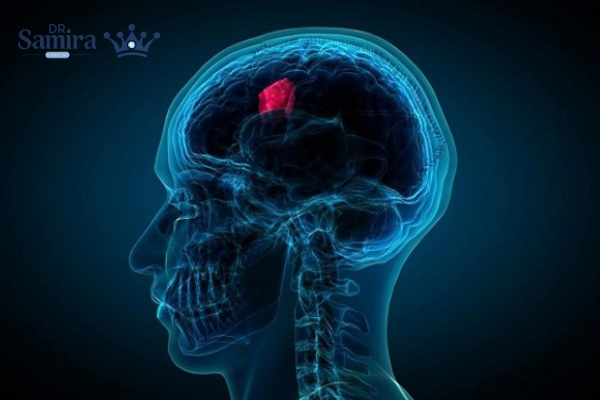

پینئوبلاستوم یکی از تومورهای نادر و بدخیم مغز است که در غدهای کوچک به نام غده پینهآل (Pineal gland) در مرکز مغز شکل میگیرد. این غده وظیفه ترشح هورمون ملاتونین را دارد که چرخه خواب و بیداری بدن را تنظیم میکند. تومور پینئوبلاستوم بیشتر در کودکان و نوجوانان دیده میشود و از آنجا که سرعت رشد بالایی دارد، در صورت تأخیر در تشخیص میتواند به سایر بخشهای مغز و حتی نخاع گسترش یابد. تشخیص زودهنگام و درمان سریع، نقش حیاتی در کنترل این بیماری دارد.

پینئوبلاستوم نوعی تومور بدخیم سیستم عصبی مرکزی است که از سلولهای نابالغ عصبی در ناحیه غده پینهآل منشأ میگیرد. این سلولها بهجای توقف رشد در زمان مناسب، به تکثیر غیرقابل کنترل ادامه میدهند و تودهای سرطانی را شکل میدهند. به دلیل قرار گرفتن غده پینهآل در عمق مغز، این تومور زمانی شناسایی میشود که اندازه آن افزایش یافته و باعث بروز علائم فشاری در مغز شده است. پینئوبلاستوم جزو تومورهای درجه چهار محسوب میشود و از تومورهای خوشخیم همان ناحیه مثل پینئوسیتوما خطرناکتر است.